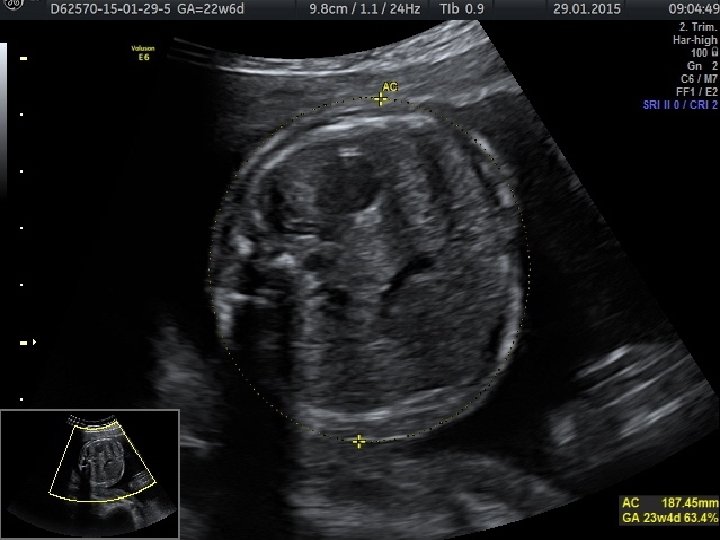

• Anormal biyometri saptanan hastalarda anormal fetal büyümenin fetal, plasental veya maternal nedenlerinin belirlenmesi amacıyla klinik ve ultrasonografik muayene yapılması gerekir. • Tahmini fetal ağırlığın saptanması için birçok formül önerilmiştir. • Bu formüllerin birçok parametre içermesine (biparietal çap, oksipitofrontal çap, baş çevresi, femur uzunluğu, abdominal çap ve abdominal çevre) karşın tahmini fetal ağırlıkta yanılma ortalama %10 -15 arasındadır ve bu oran %25’e kadar çıkabilmektedir.

• Gebelik yaşının tespitinde erken gebelikte en değerli ultrasonografik ölçüm parametresi CRL’dir. • İkinci trimesterda ise BPD ve HC daha doğru sonuçlar verir. • Üçüncü trimesterda ise en değerli ölçüm AC’dir. AC fetal büyüme ve ağırlık için en değerli parametredir.